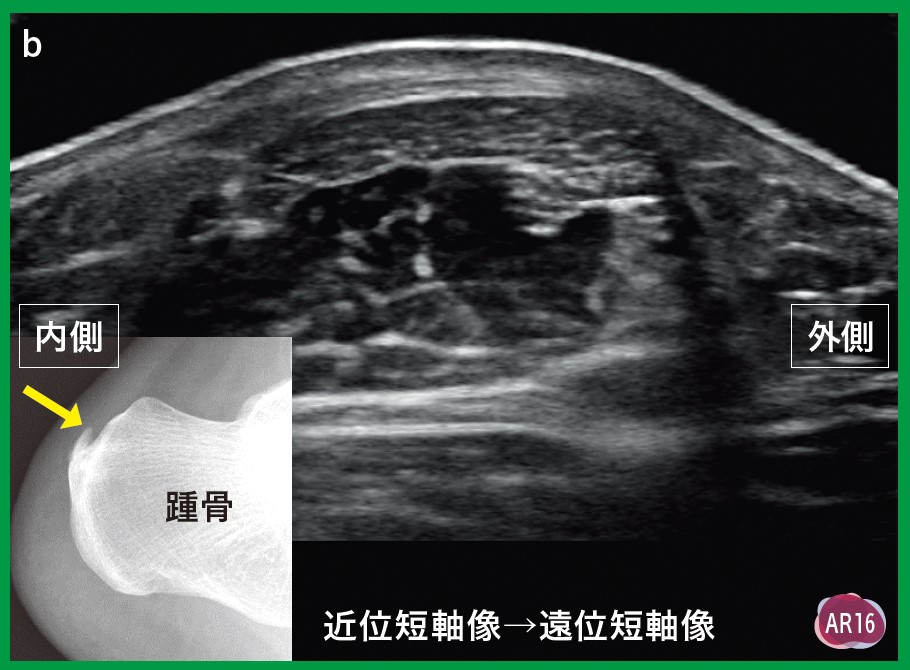

AR動画100本付きで、痛みの治療法を探る内容です。書込みなし裁断済み- タイトル: 運動器エコーのメタ診療- 特典: AR動画100本付き- 著者: 梅川直樹- 内容: 痛みをどう考え、どう治すのかご覧いただきありがとうございます。